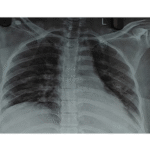

Dexamethasone is a potent synthetic glucocorticoid widely prescribed for its anti-inflammatory and immunosuppressive effects. However, long-term unsupervised use may lead to serious endocrine and infectious complications, especially in elderly individuals. We report the case of a 70-year-old male with chronic joint pain who self-medicated with over-the-counter dexamethasone (0.5 mg daily) for ten years. He developed classical Cushingoid features and presented acutely with breathlessness, abdominal pain, fever, and dysuria. Laboratory investigations showed severe hyperglycaemia, leucocytosis, renal impairment, and urinary tract infection-suggestive of systemic inflammation and sepsis. The patient was admitted to the intensive care unit and managed with broad-spectrum antibiotics, insulin infusion, and vasopressor support. He showed both clinical and biochemical improvement and was discharged after 12 days with a plan for gradual steroid tapering and endocrinology follow-up. This case highlights the dangers of long-term corticosteroid misuse without medical supervision, particularly in elderly populations, and underscores the need for early detection, pharmacist-led intervention, and structured tapering protocols.